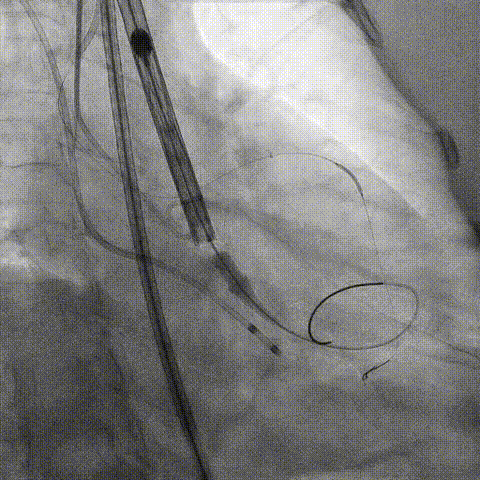

冠脉造影

手术策略和器械选择

预置Telescope™导引延长导管及导丝保护左冠,

18mm球囊预扩张再次评估冠脉闭塞风险。

Telescope™+Runthrough

18mm*40mm 预扩张

预埋 Resolute Integrity 3.5*26mm

再次评估左冠开口